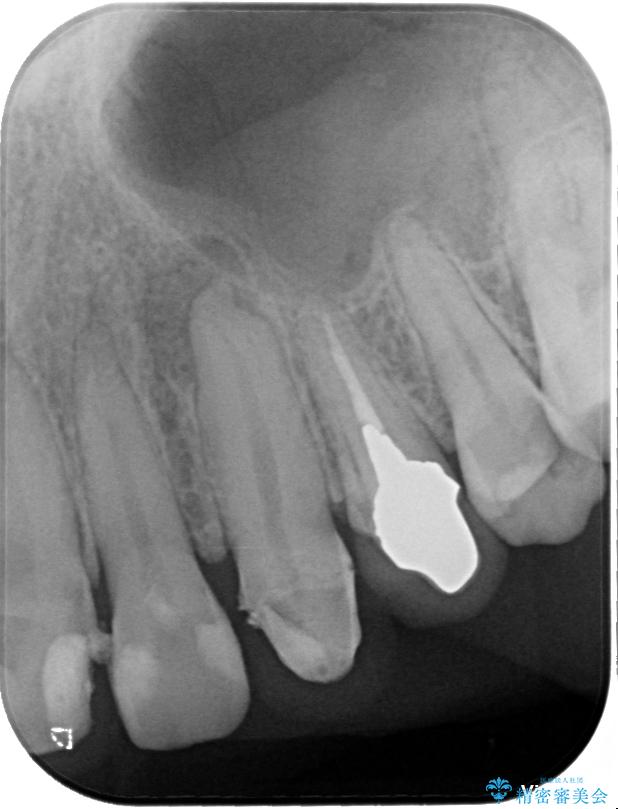

精密検査の結果、右上中切歯には**フェルール(歯の周囲の健全な歯質)**がほぼ存在せず、このままの状態での保存は困難と判断しました。

■保存治療の選択肢として**挺出(エクストリュージョン)**により歯を引っ張り出し、フェルールを確保する方法も検討可能でしたが、患者様のご希望により、より短期間で審美性を回復できる治療法を選択。

▶右上中切歯

抜歯後、即時インプラント埋入

• 「抜歯してブリッジ」と言われた20代女性が選んだ治療とは|たった4か月で自然な笑顔に抜歯即時インプラント+審美補綴の症例 治療前画像

• 「抜歯してブリッジ」と言われた20代女性が選んだ治療とは|たった4か月で自然な笑顔に抜歯即時インプラント+審美補綴の症例 治療途中画像